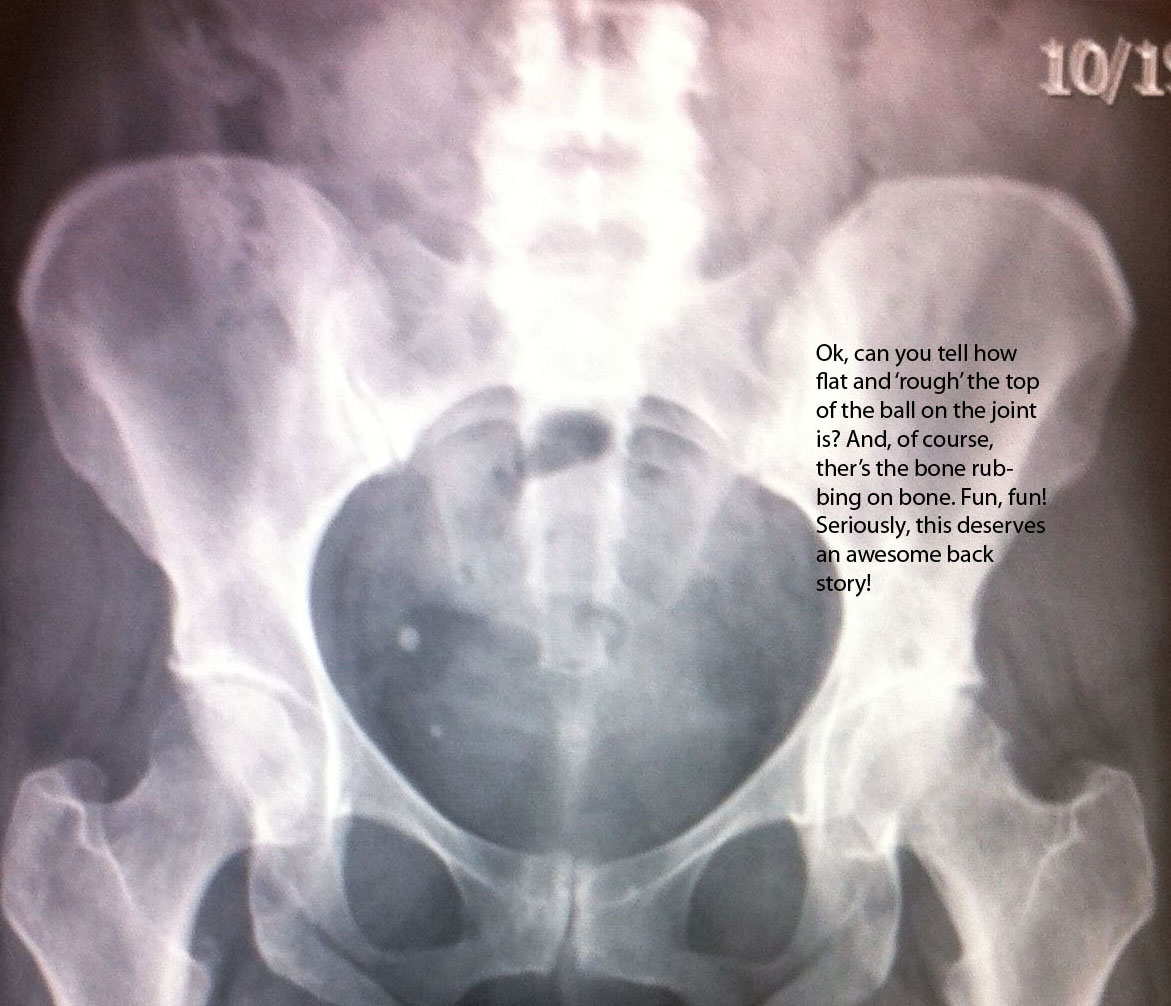

When my X-rays came back, my doc was shocked to the point of being shaken. The specialist shook his head and said he could not think of any explanation, “something just went wrong,” I ‘had the surgeon at the X-ray,’ or so it seemed. He squinted and said the word “severe” and did a couple of mobility tests then told me I’m completely messed up (well, yes, but what about my hip? Oh, right!).